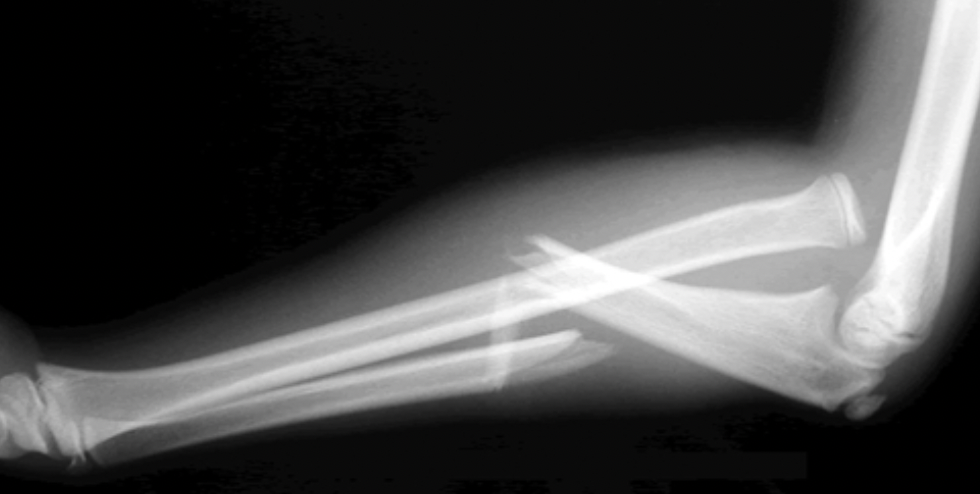

4. Monteggia Fracture

• Definition: This occurs when the ulna has a fracture and the radial head has dislocated from the elbow joint

• Special Considerations: The annular ligament is usually stretched or ruptures

• Treatment: Children can be reduced and immobilized in a cast. If the fracture is open (goes through the skin), unstable, or comminuted, it may require surgery